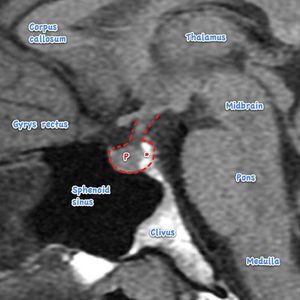

In this MRI pituitary gland and its relations are shown. Relations of the pituitary gland are important to know because spread of the tumors of pituitary gland is common, Relations go as:•Inferior: Sphenoid sinus.•Superior: Diaphragma sella, Optic chiasm.•Lateral: Cavernous sinus and its content.•Anterior: Anterior Intercavernous sinus.•Posterior: Posterior Intercavernous sinus, Pons, Basilar artery.